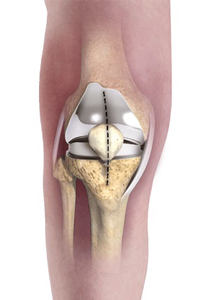

• Unicompartmental/Partial Knee Replacement

Unicompartmental/Partial Knee Replacement

Unicompartmental knee replacement is a minimally invasive surgery in which...